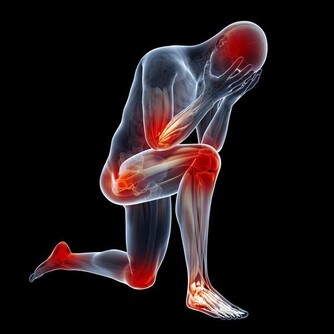

現在城市污染嚴重,霧霾多,多吃蘋果,可以增強我們的呼吸系統和心肺功能,減少煙塵對肺部的侵害。